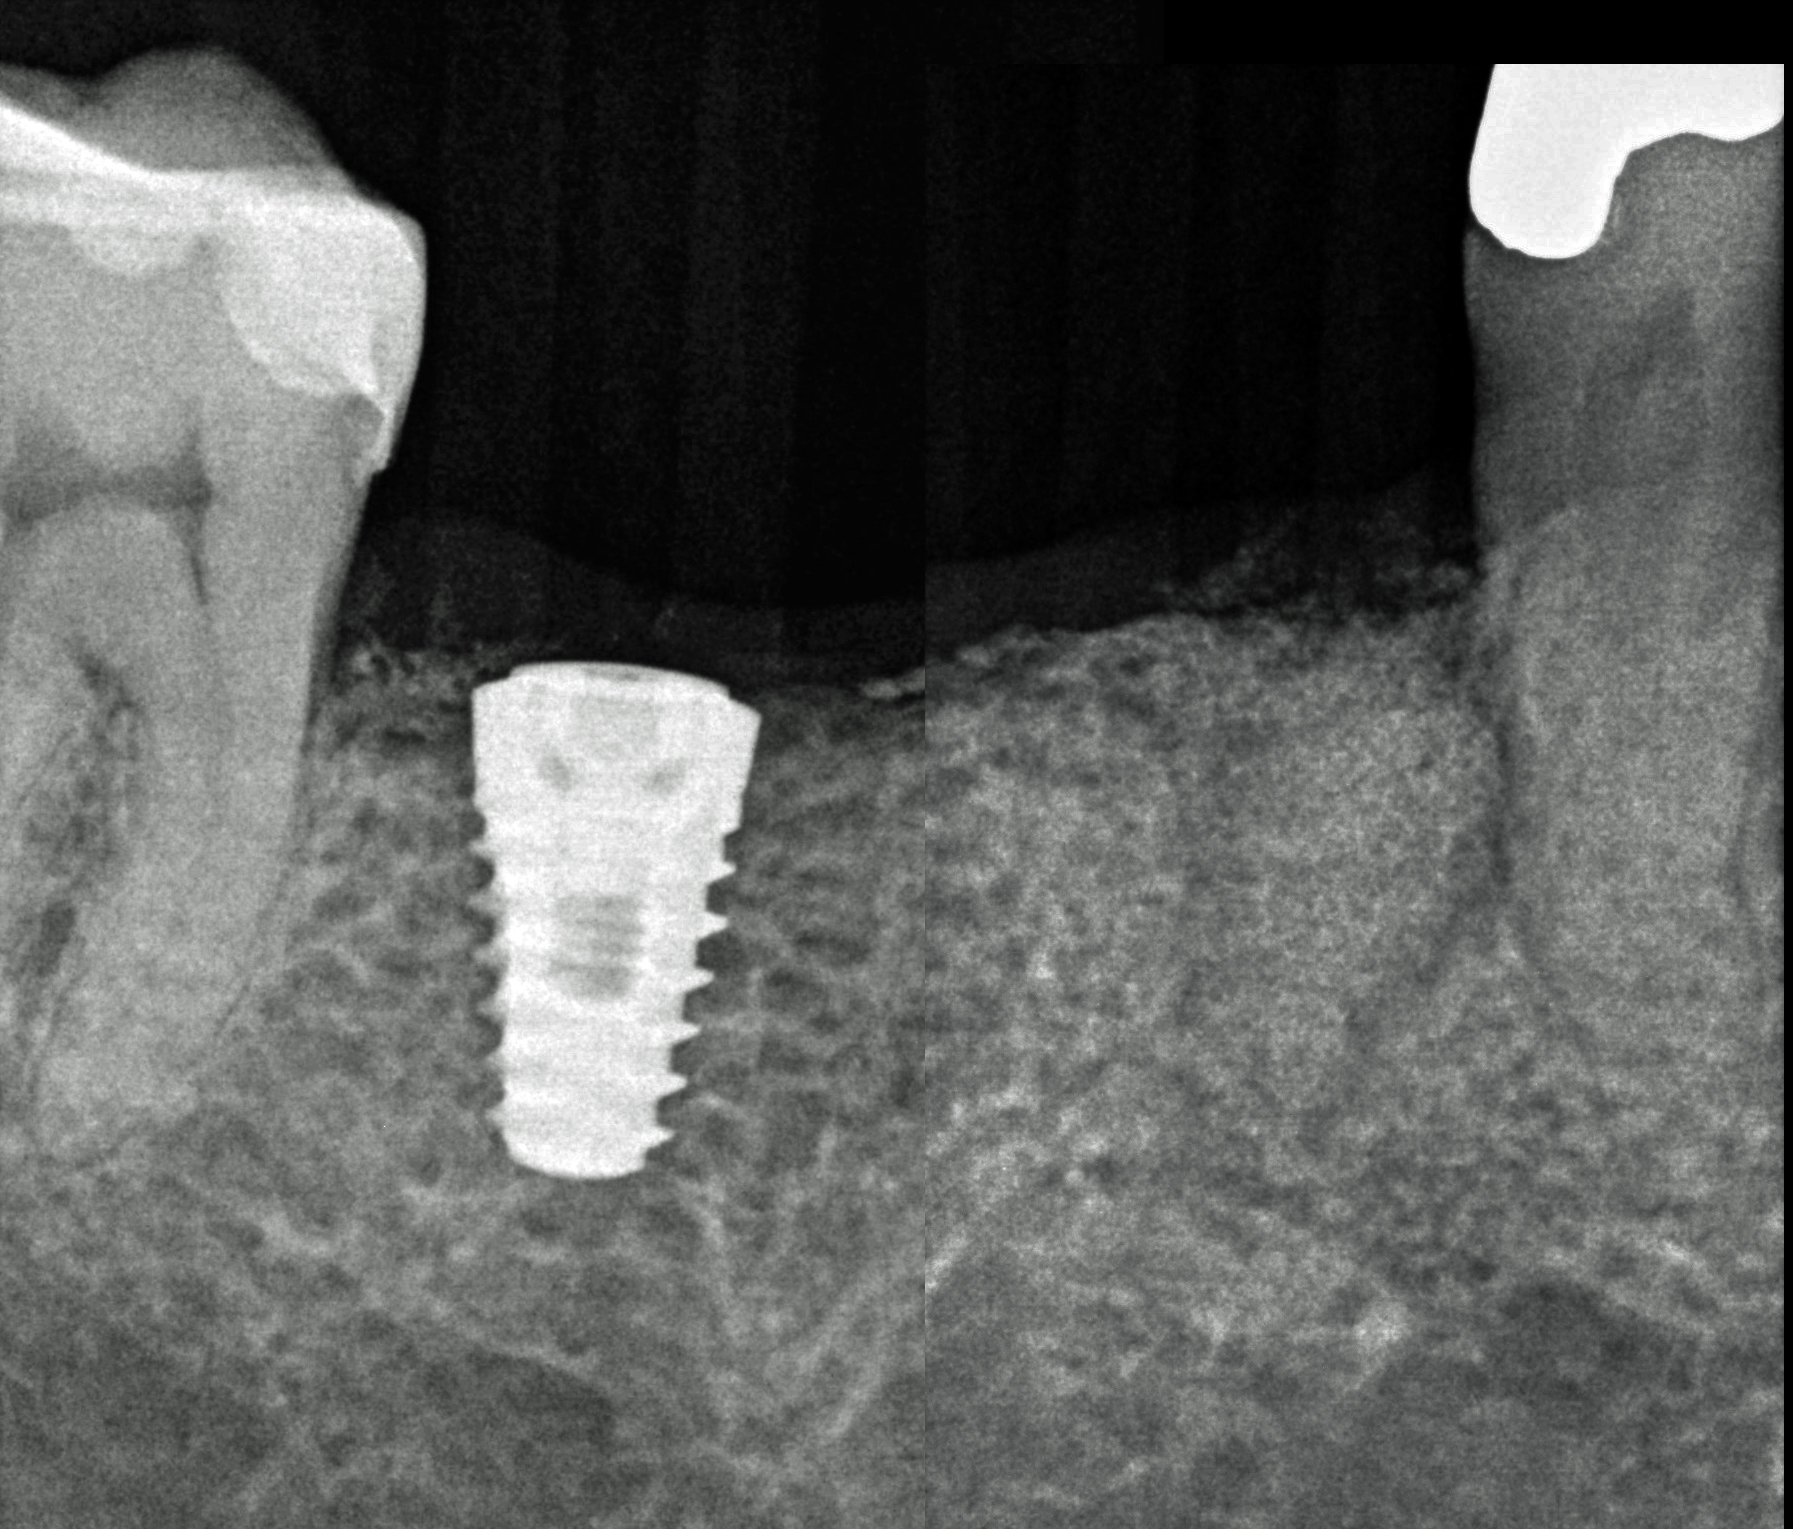

Dopo sei mesi dall’intervento di preservazione alveolare si inserisce un impianto differito in posizione 4.5.

Il tunnel implantare è molto vascolarizzato. Viene inserito un impianto Neoss Tapered 4,5x11 mm, bone level, con torque di inserimento di 60 Ncm e ISQ 75 (Figure 20-22).

Viene inserito un impianto osteointegrato Neoss Edge 5.0 x 9 mm in posizione 4.6 (Figure 13-14).